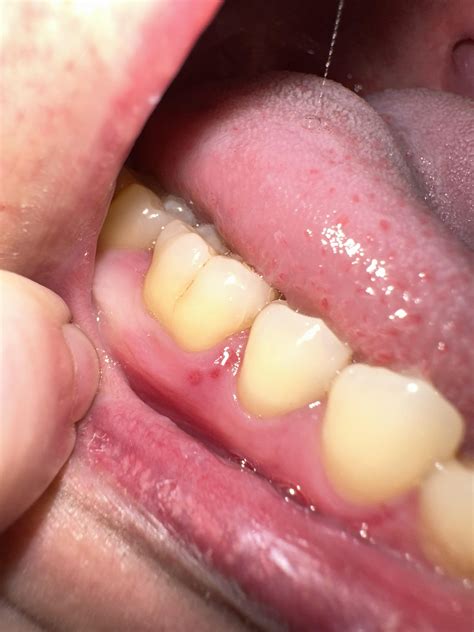

A red patch on gums can manifest in various forms and intensities. It can range from a small, localized area to a more extensive, inflamed region. The color and texture of the patch can also vary, sometimes appearing smooth or rough, and can be accompanied by pain, swelling, or bleeding. Understanding the underlying causes is the first step in addressing this issue.

• Gingivitis: This is a mild form of gum disease caused by plaque buildup. It can lead to red, swollen gums that may bleed easily.

• Periodontitis: A more severe form of gum disease that can cause deep pockets to form between the teeth and gums, leading to red, inflamed patches.

• Trauma or Injury: Physical trauma to the gums, such as from a sharp tooth or dental appliance, can result in redness and inflammation.